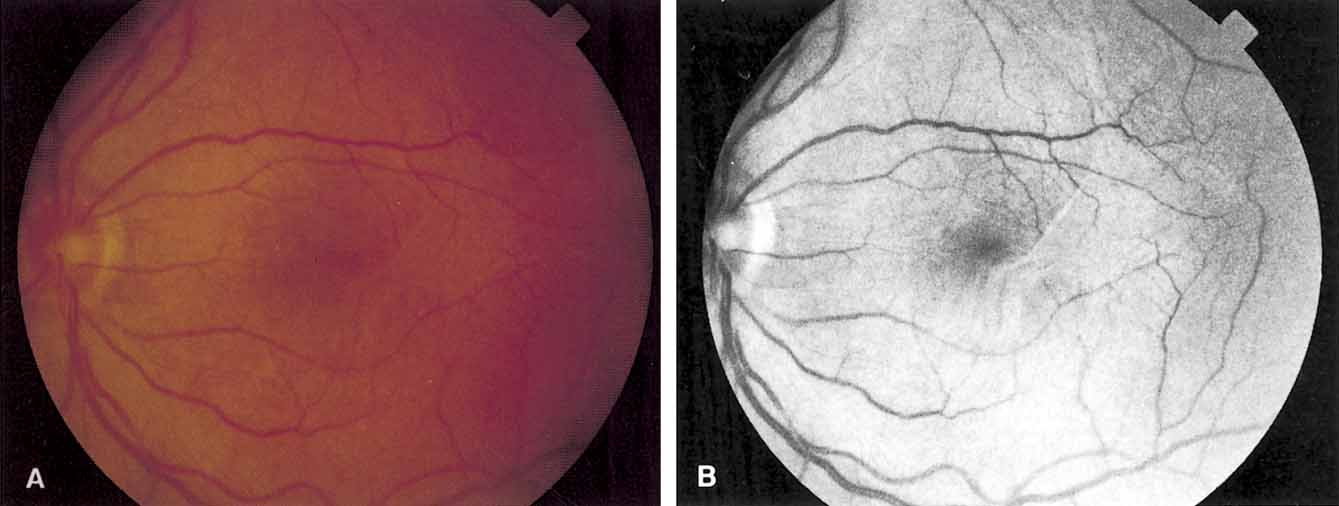

The clinical appearance is variable and may present as only a mild sheen or glint in the macular region that can best be seen with red-free or monochromatic green or blue light (Fig. 5). In more severe cases, there is increased vascular tortuosity and the perimacular vessels are seen to be pulled toward an epicenter, with striae and heterotopia of the macula. The superior and inferior arcuate vessels are also closer together and straighter than in an uninvolved eye. Other findings that may be present include small intraretinal hemorrhages, cystic changes in the macula, macular edema, and cotton-wool spots.110 Pseudoholes or macular cysts have been noted in up to 8% of idiopathic cases (Fig. 6).25,88 Thin membranes may be completely translucent, whereas thicker membranes are frequently opaque or pigmented and generally obscure details of the underlying fundus (Fig. 7).110–112 The thicker and occasionally pigmented membranes are often seen after retinal detachment surgery, severe inflammatory conditions, and trauma. An apparent posterior vitreous separation has been reported by most authors to exceed 75% in cases of idiopathic epiretinal membranes.84–88,93,104,105,113–117 It is sometimes difficult to accurately determine the vitreoretinal relationships preoperatively.

Fig. 5 A. An idiopathic epiretinal membrane in a 65-year-old man. Visual acuity was 20/25. B. Black-and-white fundus photograph taken with green 540-nm filter. Note increased definition of epiretinal membrane. (Margherio RR: Epiretinal macular membranes. In Albert R, Jakobidc EA, eds. Principles and Practice of Ophthalmology, Vol. 2. Philadelphia: WB Saunders, 1993:919–925)